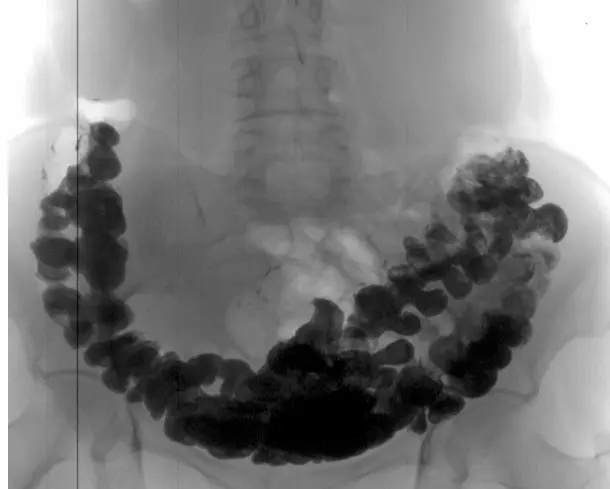

Vastagbélrák egy gyakori székrekedésre panaszkodó nőnél

A vastagbélben lévő székletkövek röntgenvizsgálata